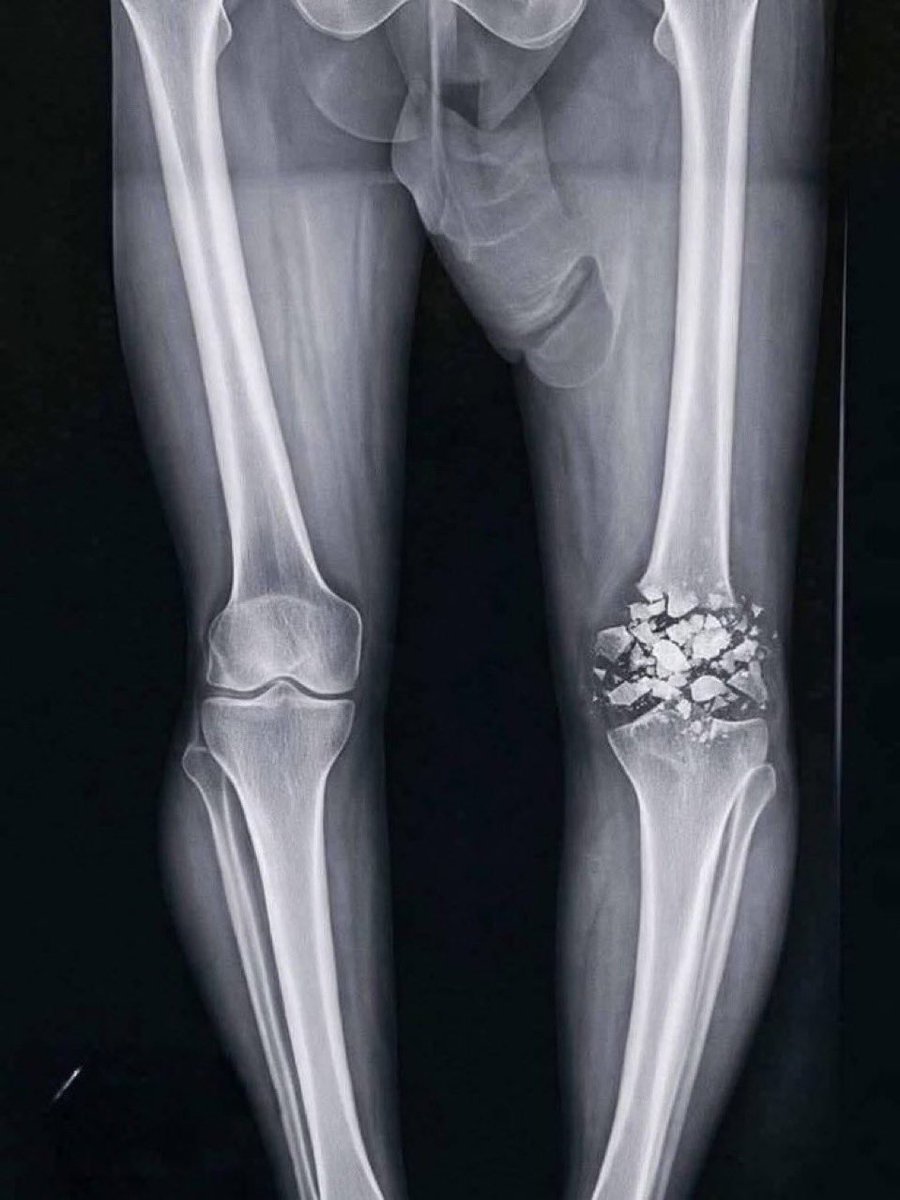

Edin Dzeko soll sich nach dem Zweikampf mit Davide Frattesi das Schlüsselbein gebrochen haben!

Nun meldet er sich selbst zu Wort und postet ein Röntgenbild: